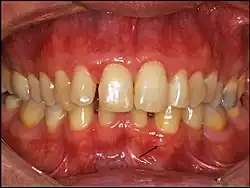

Gingival cyst of adult (arrow)

Gingival cyst of adult is a rare condition. The incidence is less than 0.5%. It is formed from the rests of dental lamina.[11] It is found in the soft tissues on the buccal and labial portions of the jaw. It usually occurs on the facial gingiva as a single small flesh colored swelling, sometimes with a bluish hue due to the cystic fluid. Sometimes, it may occur in cluster, either unilaterally or bilaterally or on the lingual surface of the alveolar process. It is most commonly seen in the canine and premolar regions of the mandible, and are sometimes confused with lateral periodontal cysts.[12] It is not normally problematic, but when it grows larger, it can cause some discomfort. It can be removed by simple surgical excision. They are developed late in life, generally up to the sixth decade of age.[1]